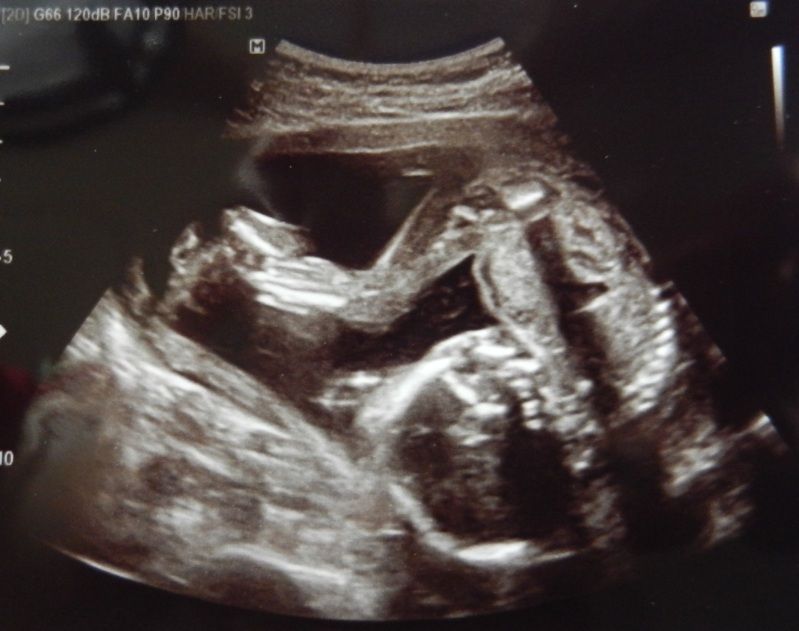

Maar goed, we zitten daar dus, die echo wordt op mn buik gezet en we zien dit.

Juist de baby die in koprol positie ligt :-/ Dus alle 3 met een vreemd gezicht naar dat scherm staren en alle 3 met het hoofd schuin. De echodame moest gniffelen en zei, ja soms tref je ze echt in de meest vreemde posities aan.

En toen de foto werd genomen zette de kleine zich net af wat ik dus echt voelde aan de buitenkant en zo werd voor mij bevestigd dat het de voetjes zijn die ik elke x voel schoppen(dacht nl misschien dat de kleine zich afzet en dat het kopje dan ergens tegenaan knalt). Wat een kracht in die minibeentjes zeg!